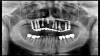

(16.) Photograph of failing implant prosthetics that may require specialty care taken with a smartphone and an EALS device.

Figure 16

(17.) Photograph of failing implant prosthetics that may require specialty care taken with a smartphone and an EALS device.

Figure 17

Emergency visits are a common and unpredictable occurrence at nearly all dental practices (Figure 14 and Figure 15). When an emergency occurs, the patient's provider may not always be available to evaluate and initiate treatment. In a similar manner, new patients of record frequently present with oral conditions that require the attention of a dental specialist who may only be available at another clinic (Figure 16 and Figure 17). For many of these patients, immediate access to care may be limited, and if a patient is experiencing discomfort, time will be a critical factor in regard to initiating a proposed plan of action. The use of a smartphone with an EALS can allow the clinical staff to rapidly acquire intraoral photographs or a video and transmit these images and other information via encrypted text message or secure e-mail to anywhere in the world for immediate consultation. The combination of telecommunications and dentistry is known as teledentistry,13which has been shown to impart significant benefits to patients and providers in the fields of oral medicine,14 oral and maxillofacial surgery,15 endodontics,16 prosthodontics,17 periodontics,18 pediatrics,19 orthodontics,20 and oral hygiene.21